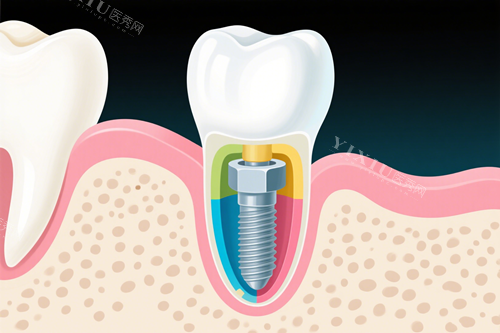

种植牙项目:

韩国登腾种植体:2980元起

瑞士ITI标准种植体:12000元起

德国ICX种植体:13000元起

NEO-biotech种植体:6500元起

瑞典NobelActive种植体:30000元起

瑞典NobelCC种植体:22000元起

瑞典NobelReplace种植体:18000元起